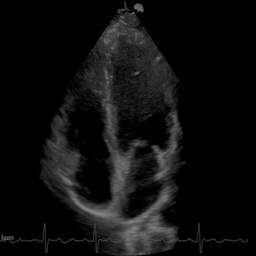

We evaluate on cardiac ultrasound videos from difficult-to-image patients using two unsupervised metrics: gCNR (contrast between ventricle and septum regions) and the KS statistic (agreement between original and denoised tissue distributions). Higher gCNR indicates better haze suppression; lower KS indicates better signal preservation.

Qualitative comparison on cardiac ultrasound dehazing. While both methods suppress haze (shown in the insets), RPCA tends to excessively attenuate tissue, resulting in sparse structures, whereas Nuclear Diffusion better preserves anatomical detail.